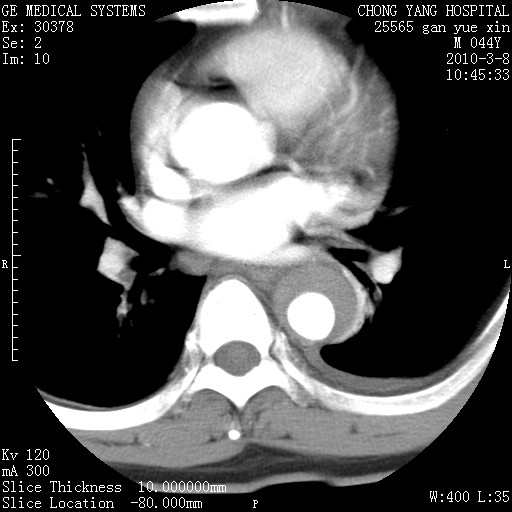

标题: CT24940:主动脉增强,典型病例。 [打印本页]

标题: CT24940:主动脉增强,典型病例。

夹层动脉瘤。

动脉夹层

夹层动脉瘤,典型

主动脉夹层。

动脉夹层的分型:

⒈debakey分型:根据主动脉夹层累及部位,分为三型:ⅰ型:原发破口位于升主动脉或主动脉弓部,夹层累及升主动脉、主动脉弓部、胸主动脉、腹主动脉大部或全部,少数可累及髂动脉。ⅱ型:原发破口位于升主动脉,夹层累及升主动脉,少数可累及部分主动脉弓。ⅲ型:原发破口位于左锁骨下动脉开口远端,根据夹层累及范围又分为ⅲa,ⅲb。ⅲa型:夹层累及胸主动脉。ⅲb型:夹层累及升主动脉、腹主动脉大部或全部。少数可累及髂动脉。

⒉stanford分型:a型:夹层累及升主动脉,无论远端范围如何。b型:夹层累及左锁骨下动脉开口以远的降主动脉。

夹层动脉瘤,少量胸水

夹层动脉瘤;左侧少量胸腔积液。